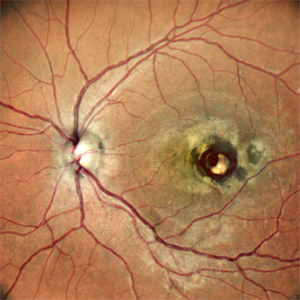

Childhood Acquired Ocular Toxoplasmosis

Childhood Acquired Ocular Toxoplasmosis

Sep 13 2023 by Deepak Bhojwani, MS

Fundus image of a 16 year old boy diaagnosed with Ocular Toxoplasmosis since the age of 10 years showing the classic toxo chorioretinitis scar on the posterior pole. Luckily the scar is loacted juxtatemporal to fovea on OCT and so the boy has good vision of 20/30.

Photographer: DR DEEPAK BHOJWANI

Imaging device: OPTCAL COHERENCE TOMOGRAPHY

Condition/keywords: posterior uveitis, toxo chorioretinitis